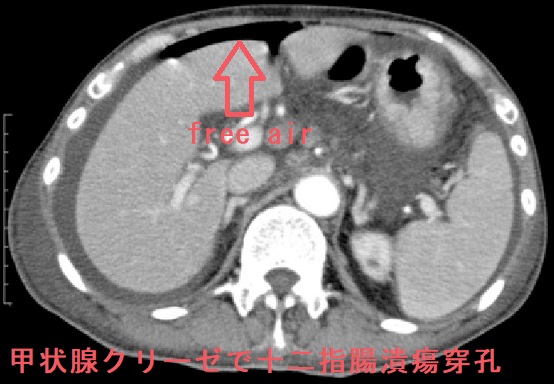

意外と知られていませんが甲状腺クリーゼの死因の5%は消化管穿孔(胃腸が破けること)です(Thyroid. 2012 Jul;22(7):661-79.日本甲状腺学会の統計です)。(甲状腺クリーゼの胃潰瘍穿孔、十二指腸潰瘍穿孔、大腸穿孔)

消化管潰瘍(胃十二指腸潰瘍)穿孔を発症すると、腹部単純CTにおいて

- 遊離ガス像(free air)

- 胃壁外に消化液や食物残渣

を認めます。 絶食・輸液・経鼻胃管挿入を行い、抗菌薬やプロトンポンプインヒビターを投与。従来は緊急手術が必須とされていたが、現在では保存的治療で緩解するケースも多い。緊急手術するとしても、甲状腺クリーゼの状態なので、かなり厳しい手術になります[成功例も報告されています(Case Rep Endocrinol. 2015;2015:750390.)]。